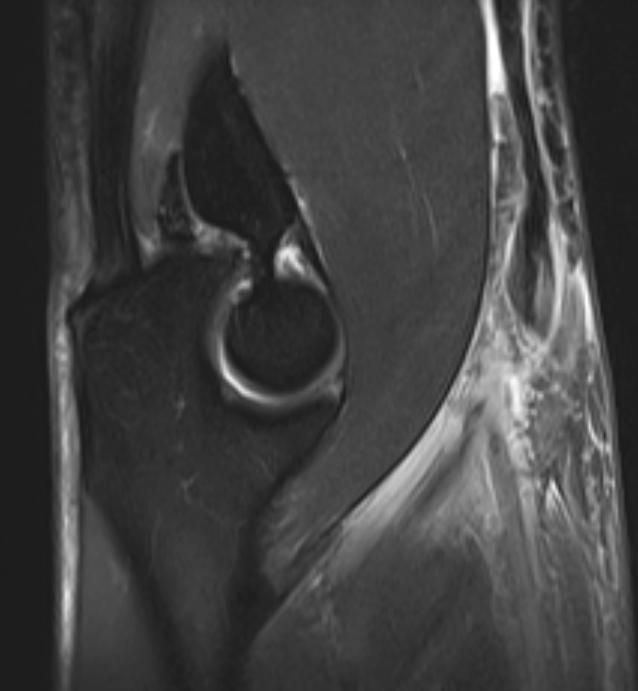

3. Lacertus fibrosus injury (biceps)